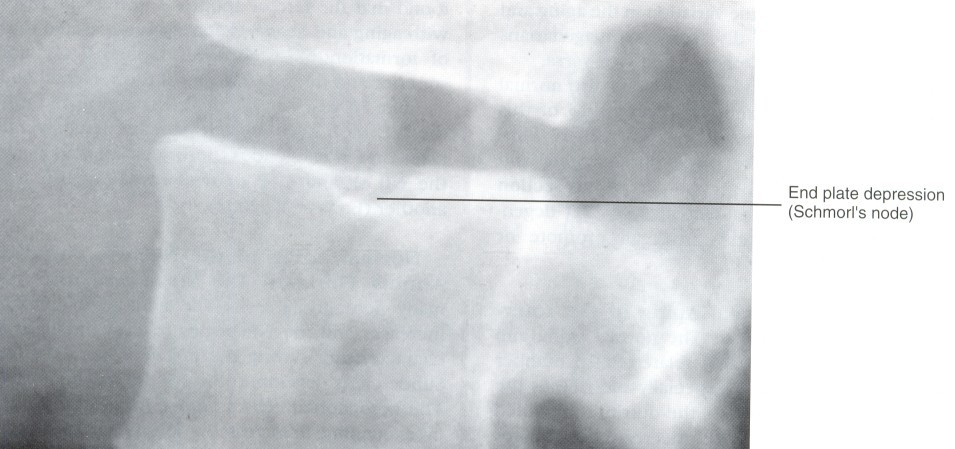

Schmorl's node

Schmorl's nodes are defined as heerniation of the IVD through the CEP and bony end flate.

these lesions are believed to be associated with trauma and occur most frequently in the lower thoracic and lumbar region

Even though trauma is the most likely cause of Schmorl's node formation, a possible congenital origin, such as notochondrial cell "rests"(pockets of notochondral bone adjacent to the CEP, also been suggested

such congenital defects could predispose one to later CEP fractures